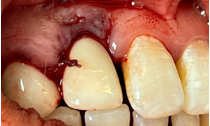

2 months after sealing (Figures 23–27). In implantology, connective tissue grafting is indicated at all stages of implant therapy to guarantee an optimal aesthetic result. Connective tissue tunnel grafts has been chosen. After 2 months of surgery, we note a good aesthetic result and the satisfaction of the patient.

Figure 24 Palatal graft harvesting.

Figure 25 Graft fixation+sutures.